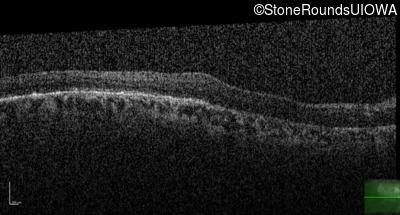

Age at visit: 55 years